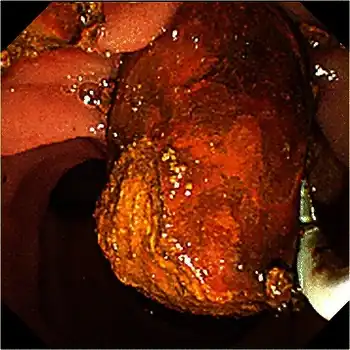

Abdominal ultrasonography of a common bile duct stone